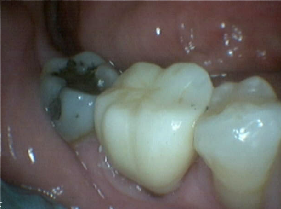

Bruxir Crown, Fractured Alloy